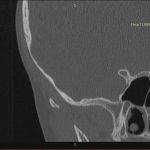

- Diagnosticul traumatismelor de bază de craniu

- Diagnosticul fracturilor:

-

- Unice

- Multiple

- Cu înfundare

- Complexe cranio-sinusale

- Complexe cranio-etmoidale

- Complexe cranio-orbitare

- Complexe cranio-faciale